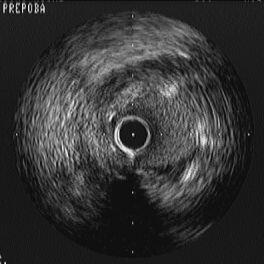

ウチの症例をひとつ提示します。70歳代の男性。RCA#2に対してrt TRIを行いまし

た。LADにcollatralがありますが、もちろん、RCAを仕上げたあとで、LAD#7 CTOもあ

けるつもりでした。LAD遠位部近位端へのcollateralはconusからでていて、microに

よるsuper-selectiveな対側造影が望ましい形です。RCA近位部はShepherd's crookな

のでLauncher 6Fr JL4.0-SHを反転させていれました。このとき、RCA入口部の下に

わずかに造影剤のたまりがあります(Fig1)。RCAはひどいaccordionを呈しました

が、無事にCypherをいれ、ワイヤを抜いたところ急性冠閉塞となりました。

Runthroughでre-crossしようとしましたが、入り口からtrueはほとんど圧排されてい

るようで、false、それもRCA本幹から相当はなれたところにしか入りません

(Fig2)。そこで、このRunthouthをダミーワイヤとして解離腔の盲端に押し付けカテ

先を浮かし、苦労して探ったところ何とかtrueにre-crossし、IVUSによる観察を行い

ました(Fig3)。その後は、入口部までCypherさらに2本でfull metalにして無事に

bail outしました(Fig4)。

IVUSですが、Fig5は最初のCypherの近位側、大きくextra-vascular hematomaが広

がっているところです。3時方向にダミーでいれたRunthroughが観察されます。さら

に近位部にもどしたところがFig6、RCAを全周性にhematomaが取り囲んでいます。Fig

7は、ちょうどカテ先からでたばかりのところで、まだワイヤはtrueですが、すでに

perivascular tissueと連続した、extra-vascular hematomaが見られます。